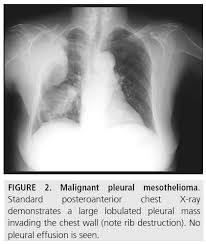

Malignant Pleural Mesothelioma Radiology Case Radiopaedia Org

Malignant Pleural Mesothelioma Radiology Case Radiopaedia Org from prod-images-static.radiopaedia.org